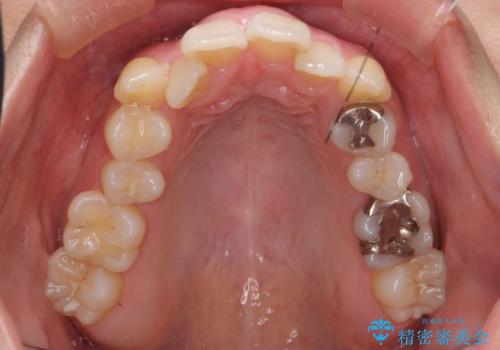

- 20代女性

- 治療計画

- 前歯のがたつきと正中のずれを主訴に来院。

小臼歯を4本抜歯しています。

歯を抜いたことで、口元が下がって、横顔も理想的なラインになりました。